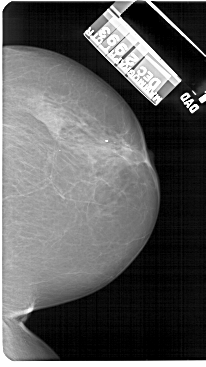

A_1565_1.RIGHT_MLO

LEFT_MLO LINES 5491 PIXELS_PER_LINE 3511 BITS_PER_PIXEL 12 RESOLUTION 43.5 OVERLAY